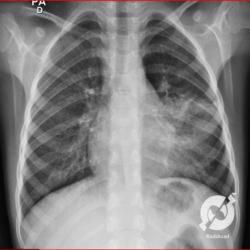

Os agentes etiológicos infecciosos são variados (bactérias, vírus, fungos, parasitas…), mas o que ocorre nos pulmões durante uma infecção por qualquer tipo de agente é a substituição do ar alveolar por secreção (pus, muco, eventualmente sangue ou necrose…) e com isso a manifestação radiográfica vai ser a mesma já que todas estas secreções apresentam a mesma densidade radiográfica: partes moles.

E o nome dado a esta alteração radiográfica que corresponde à substituição do ar alveolar por líquido é a consolidação alveolar.

Uma consolidação alveolar é, por definição, uma opacidade (imagem densa, branquinha) homogênea ou às vezes heterogênea (pela presença de calcificações ou cavidades), de limites mal definidos, exceto quando toca a pleura da parede ou das cissuras pulmonares. É um termo usado tanto em radiografia, como em tomografia computadorizada. Na tomografia, um outro termo é usado: vidro fosco, que é uma opacidade (branquinha mas não tanto como a consolidação), que borra o pulmão mas deixa ver os vasos de permeio (igual bigode de adolescente: dá pra ver todo o fundo).

Nós vamos mostrar aqui um pequeno apanhado de pneumonias de variados agentes, em diversos segmentos e lobos pulmonares, com extensões variadas. O objetivo é identificar o padrão radiológico de consolidação alveolar e não determinar o agente infeccioso, isso vai ser assunto para mais adiante. Aliás já antecipo que é fundamental saber localizar a lesão, porque alguns destes bichos gostam de determinados segmentos, alguns tumores também têm as suas preferências, então localização é fundamental. Se localização não fosse importante, um apartamento na beira do mar sairia o mesmo preço de um apartamento de frente pra BR-101, concordam?

Seguem alguns dos nossos casos de pneumonia para vocês treinarem os olhos e não se apavorarem nos plantões.